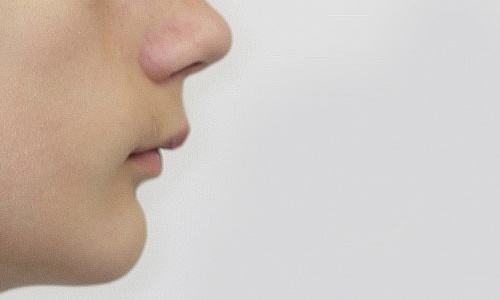

Растущий пациент. Дистальный глубокий прикус (нижняя челюсть меньше по размерам, чем верхняя). Лечение с использованием аппарата Twin Block и брекет-системы Damon-Q. Срок лечения 2 года.